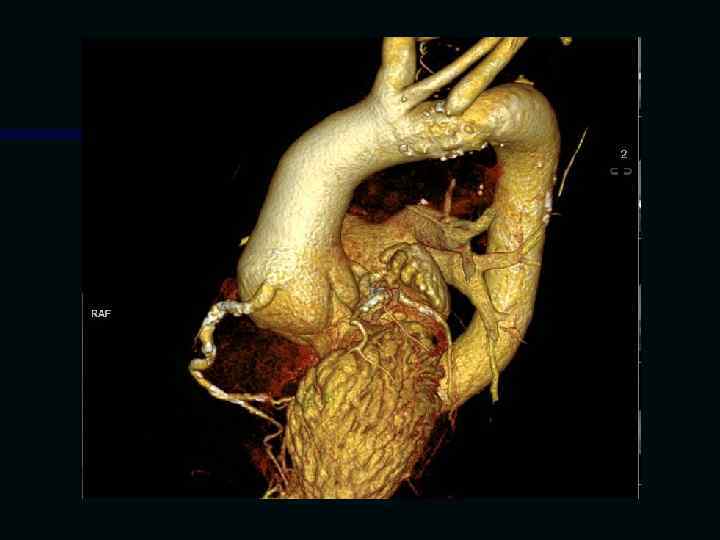

Исследование сосудов грудной клетки

Исследование сосудов брюшной полости